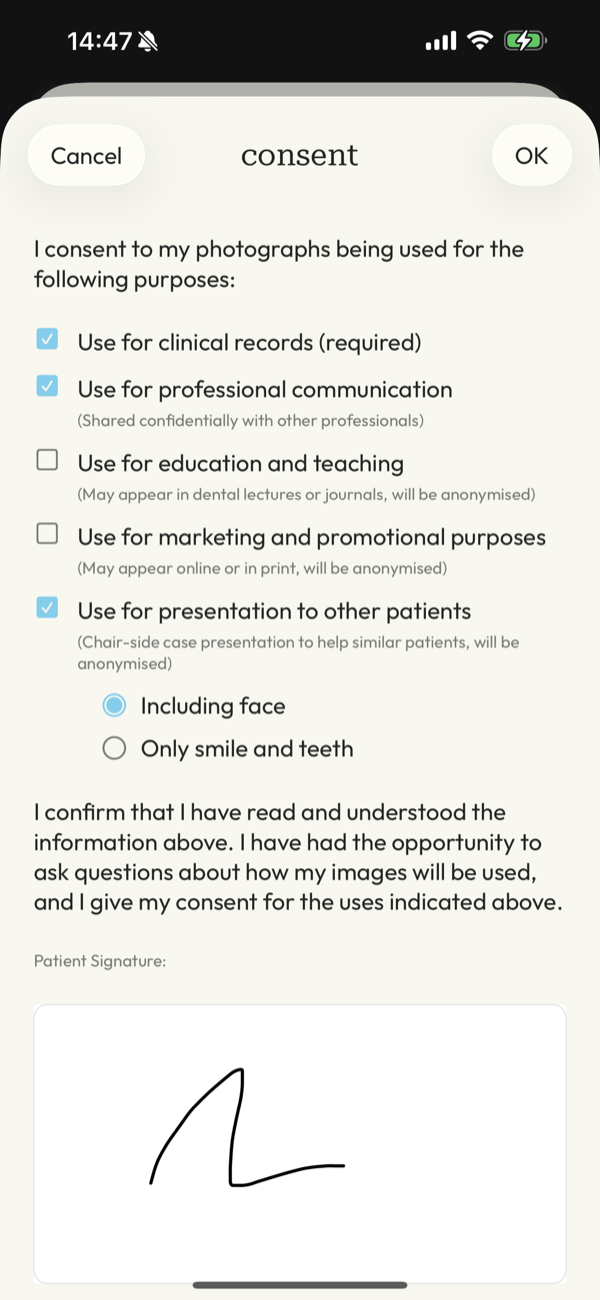

What about consent and GDPR?

Handled as part of the workflow.

DentalFolio supports structured consent recording, allowing documentation of how images are intended to be used, such as for clinical records or education. A clear audit trail is maintained if needed.

Responsibility remains with the clinician. The app supports good practice but does not replace professional judgement.